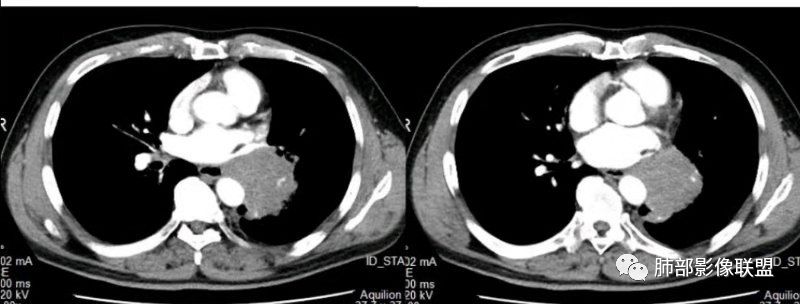

1.左下肺门区巨大肿块,支气管显示不清,轻度阻塞性炎症,没有明显肺不张,提示管腔受压狭窄可能性大于堵塞,这较少见于鳞癌。

2.病灶边缘光滑,未见明显分叶、毛刺,未见明显强化,这符合腺癌影像学特点,却符合神经内分泌癌表现。

3.病灶内密度均匀,轻到中度均匀强化,大病灶未见明显液化坏死区及空洞,不符合鳞癌而符合小细胞肺癌特点。

4.病灶内有肺动脉走形,血管局部受压,未见破坏,病灶乏血供,呈血管包埋或血管造影征;侵袭性力强及破坏力弱、血管漂浮都符合SCLC,所以鳞癌的可能性也不大。

5.左肺门块影或淋巴结肿大,竭力挤兑肺门血管结构,呈冰冻肺门;有时候SCLC可以单独呈现冰冻肺门,而没有没有冰冻纵隔。